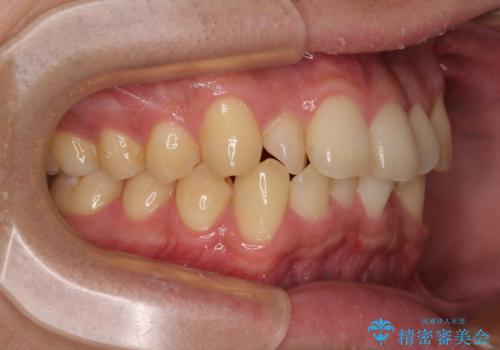

- 上下前歯の捻れやデコボコを気にして来院された患者様です。

マウスピース矯正でもワイヤー矯正でも対応可能でしたが、極力楽をして治したいとのことでワイヤー装置にて治療をおこなうこととしました。

口元はそれほど突出しておらず、患者様自身も気にしていらっしゃいませんでしたが、前歯の捻れやデコボコを解消すると、前方に拡大され、治療後に出っ歯仕上がりとなるリスクがあったため、補助装置により上顎臼歯を後方移動していくこととしました。